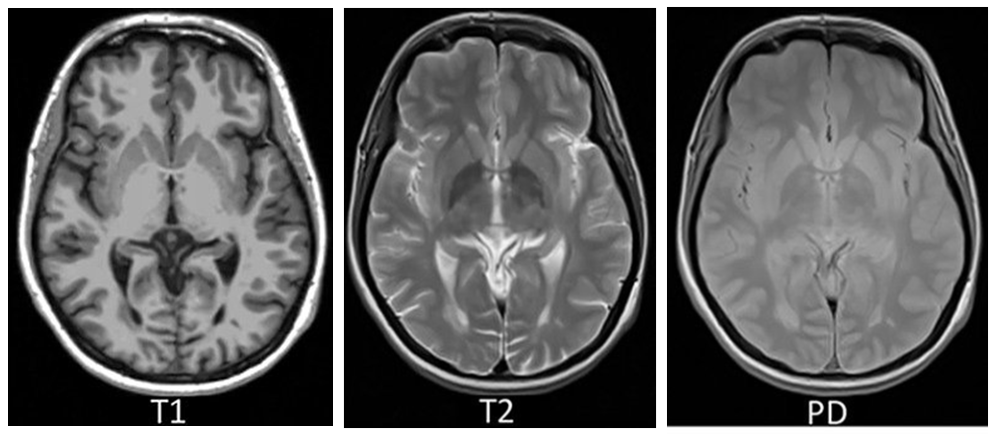

5.2. Основные анатомические серии (T1W, T2W, PdW)

Контрастность тканей зависит от различий в восстановлении продольной намагниченности (T1). Поэтому такие изображения называют Т1-взвешенными.

Контрастность ткани зависит от различий в восстановлении поперечной намагниченности (T2). Поэтому такие изображения называют Т2-взвешенными.

Эффекты Т1- и Т2-взвешенности отсутствуют или минимальны, контрастность тканей зависит от локальной протонной плотности. Поэтому такие изображения называют протонно-взвешенными или средневзвешенными.

Поскольку протонная плотность является наименее вариабельным параметром по сравнению с временами Т1 и Т2, то и контраст таких изображений ниже. Поэтому при диагностике наиболее информативными являются T1W и T2W серии, а необходимость в PdW возникает редко, обычно в ортопедии или неврологии.

Однако нужно учитывать, что на любом изображении контраст всегда зависит от всех трех параметров – времен Т1 и Т2, а также протонной плотности. Просто вклад этих параметров различен. И, поскольку значения ТR и ТE можно выбирать любыми, жесткой границы между рассмотренными сериями провести невозможно.

Значения TR и TE подбираются под каждую конкретную задачу, чтобы усилить контраст нужных для данного исследования тканей. Например, применение очень больших TR и TE дает сильно взвешенные по T2 изображения — т.н. «миелоурографический» режим (MYUR). В этом режиме хорошо визуализируются как нормальные структуры с большим содержанием свободной жидкости, так и патологические, например, ликворные кисты [5].